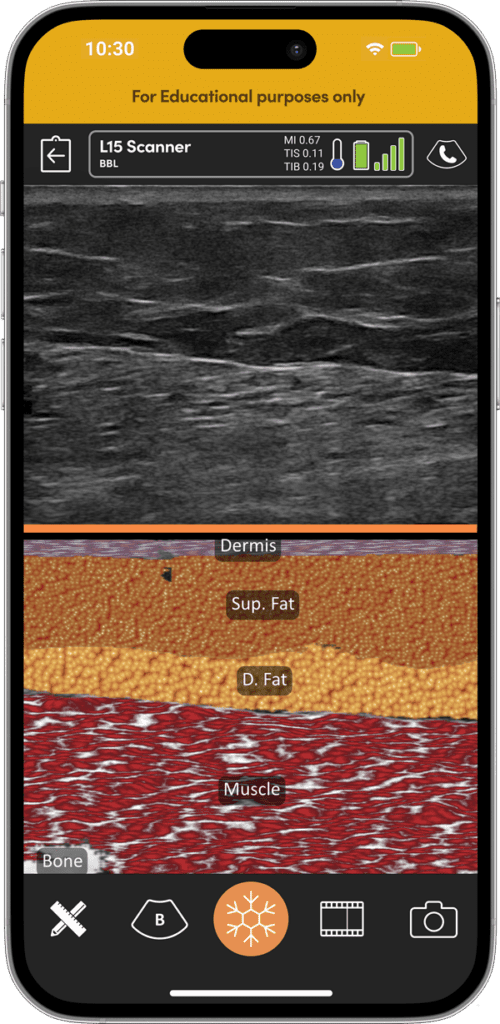

AIによる組織層の視覚化で臀部の解剖学的構造をマスターし、脂肪移植手技の学習曲線を強化します。

真皮、皮下脂肪、乳房組織、筋肉、インプラントをAIで可視化し、瞬時に見分けることができます。

BBLの必須要件となった、全長にわたる手技記録の統合により、法令遵守と患者の安全性を確保します。